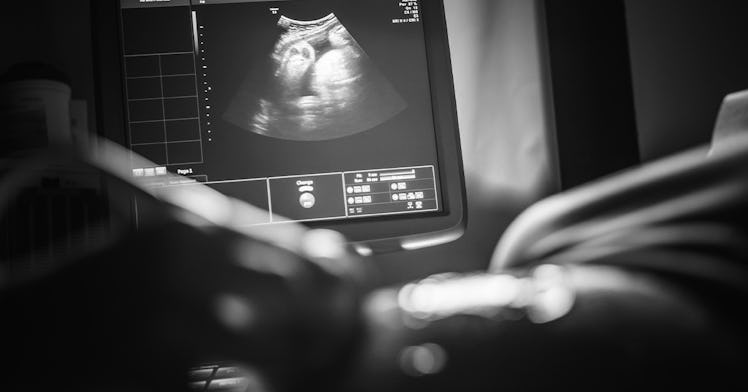

Our doctors and nurses were no better. Nobody declines an ultrasound, one nurse informed us as we sat, resolute, in a Westchester medical office. They’re simple and painless! You can frame the chalky images and show off your insectoid blob of a legacy! Second trimester ultrasounds, she added, can catch defects that modern medicine can sometimes fix. One well-timed ultrasound could save a life.

Nobody declines an ultrasound, but maybe more people should. While medical organizations and insurance companies agree that most low-risk pregnant people need only one ultrasound per pregnancy (the second trimester “anatomy scan”), studies suggest that the average American mother-to-be gets more than four before her due date and that almost all pregnant people sit for first and third trimester ultrasounds. That’s not even counting the women who pay for prenatal family photos, taken by amateurs in malls or bodegas.

Dads may be amused. Doctors, not so much. “Exposing the fetus to ultrasound energy with no anticipation of medical benefit is not justified,” according to a 2016 practice bulletin from the American Board of Obstetrics and Gynecology. “Although there is no reliable evidence of physical harm to human fetuses from diagnostic ultrasound imaging using current technology, casual use of ultrasonography, especially during pregnancy, should be avoided.” So ABOG gets its knickers in a twist because ultrasounds are powerful diagnostic tools, not toys. But, even so, what’s the harm?

But that doesn’t mean we should be zapping baby bumps willy nilly. Ultrasonography, like all diagnostic medicine, should be evidence-based and deliberate. Women with certain types of high-risk pregnancies should get multiple ultrasounds. Everyone should get the second trimester ultrasound, which is medically necessary and can save lives. And nobody with a low-risk pregnancy should be getting a first trimester ultrasound, unless there’s a specific reason for the procedure.